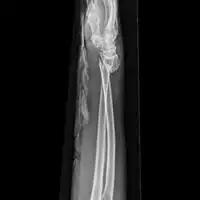

Front view of bowing fractured radius and ulna